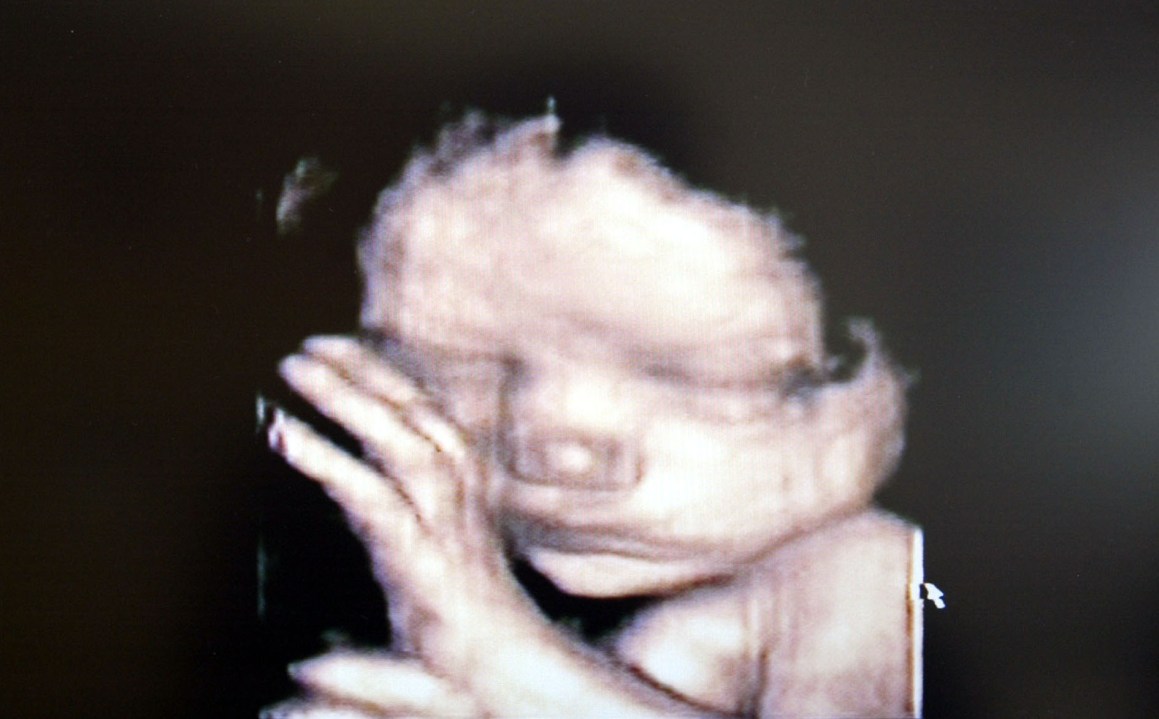

The abortion debate continues, but with the continued absence of the key statistic. How many pregnancies in this country end in an abortion? In my experience, people guess at around 10% or lower. In fact it’s is one in four in England (26.1%) and one in three in London (33%). It’s hard to consider these statistics, from any perspective, without thinking something has gone badly wrong. The 1967 Act was intended to stop Vera Drake-style backstreet abortions, not provide a medical alternative to contraception.

The extent of abortion is seldom understood because the data is couched in a way no one can understand (17.8 many terminations per 1,000 women, whatever that means). But a meaningful figure may be a little too vivid for a debate still stultified by understandable squeamishness. I’ve never worked out why our MPs are so exercised by saving foxes, but recoil from the debate about where human life begins. As Dr Evan Harris and Ann Widdecombe agreed this morning, the debate is long overdue.